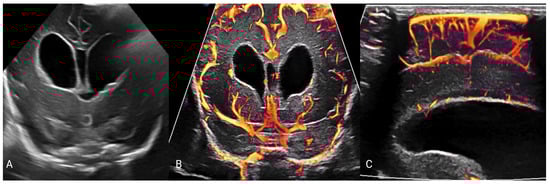

- Hwang, M.; Zhang, Z.; Katz, J.; Freeman, C.; Kilbaugh, T. Brain contrast-enhanced ultrasonography and elastography in infants. Ultrasonography 2022, 41, 633–649. [Google Scholar] [CrossRef]

- Barletta, A.; Balbi, M.; Surace, A.; Caroli, A.; Radaelli, S.; Musto, F.; Saruggia, M.; Mangili, G.; Gerevini, S.; Sironi, S. Cerebral superb microvascular imaging in preterm neonates: In vivo evaluation of thalamic, striatal, and extrastriatal angioarchitecture. Neuroradiology 2021, 63, 1103–1112. [Google Scholar] [CrossRef] [PubMed]

- Freeman, C.W.; Hwang, M. Advanced ultrasound techniques for neuroimaging in pediatric critical care: A review. Children 2022, 9, 170. [Google Scholar] [CrossRef] [PubMed]